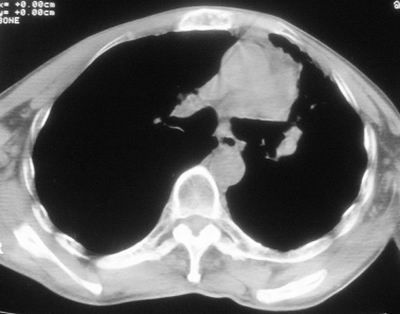

标题: CT11864:男,47岁,反复咳嗽、咯痰、咯血3年,请分析. [打印本页]

患者,男,47岁,反复咳嗽、咯痰、咯血3年,再发5天。痰培养未找到真菌、抗酸杆菌、癌细胞。

左肺上叶体积明显缩小,其内见多发透光区,纵隔向左侧移位,左肺下叶多发班片状病灶,边界模糊,1左肺上叶先天肺发育不全,2左肺下叶肺炎,

左肺上叶结核伴肺纤维化,纵隔移位,左肺下叶感染性病变,建议抗炎抗结核后复查,双肺气肿.

以下是引用xulianj在2008-2-25 21:01:00的发言:[br]左肺上叶结核伴肺纤维化有霉菌球形成,纵隔移位,左肺下叶感染性病变,建议抗炎抗结核后复查,双肺气肿.

考虑:左肺慢纤伴霉菌球形成、双肺全小叶型肺气肿。

1)考虑为:左肺上叶肺结核(空洞形成),伴左下肺感染;不排除霉菌感染可能。2)肺气肿。

左肺上叶结核伴肺纤维化空洞形成并左肺下叶感染,纵隔牵拉移位,建议作进一步检查排除左侧肺霉菌感染可能。